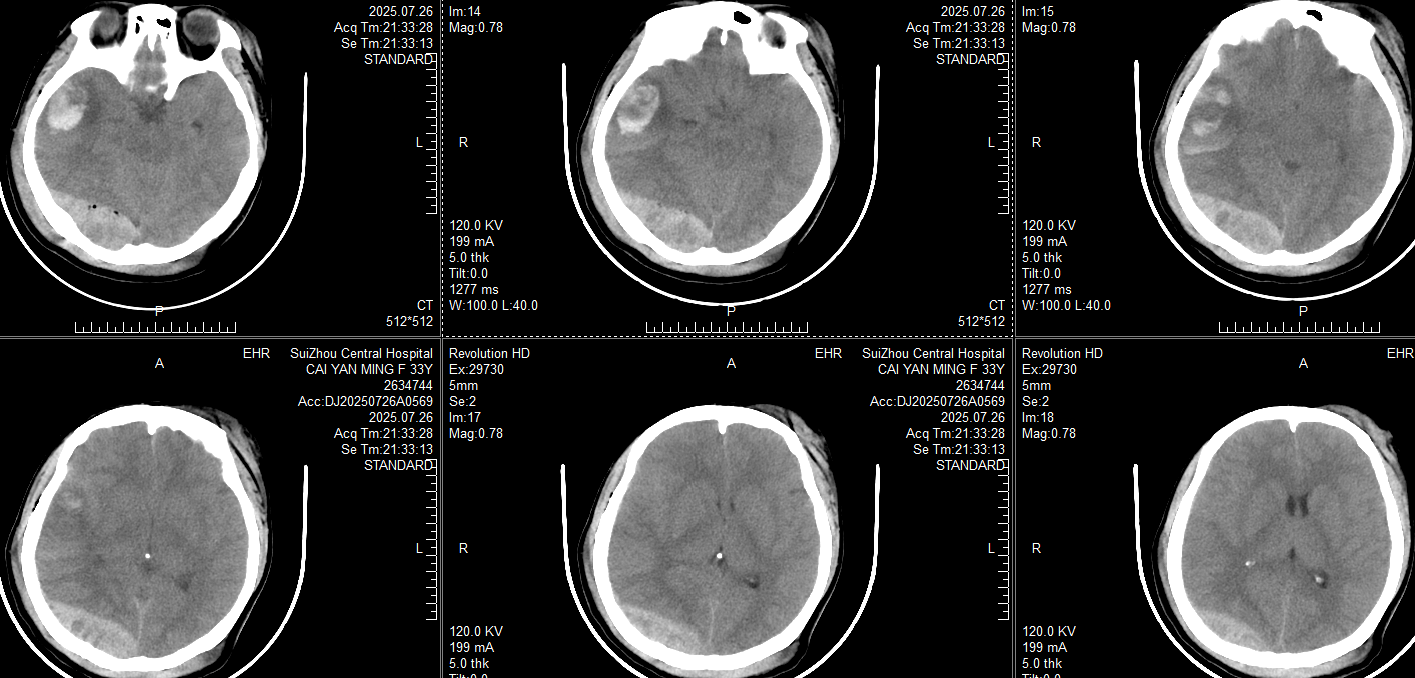

入住ICU后镇痛镇静、气管插管,止血、抑酸、预防癫痫、抗炎对症治疗;21:33复查CT:

此时患者瞳孔等大同圆直径约2mm,对光反射均存在,颞叶血肿未完全形成,在和家属交代开颅手术方案:右侧枕部开颅清除硬膜外血肿去骨瓣减压,后再复查CT对比右侧颞叶出血进展情况。家属还在考虑手术方案时,23:20患者右侧瞳孔开始放大,立即复查CT: